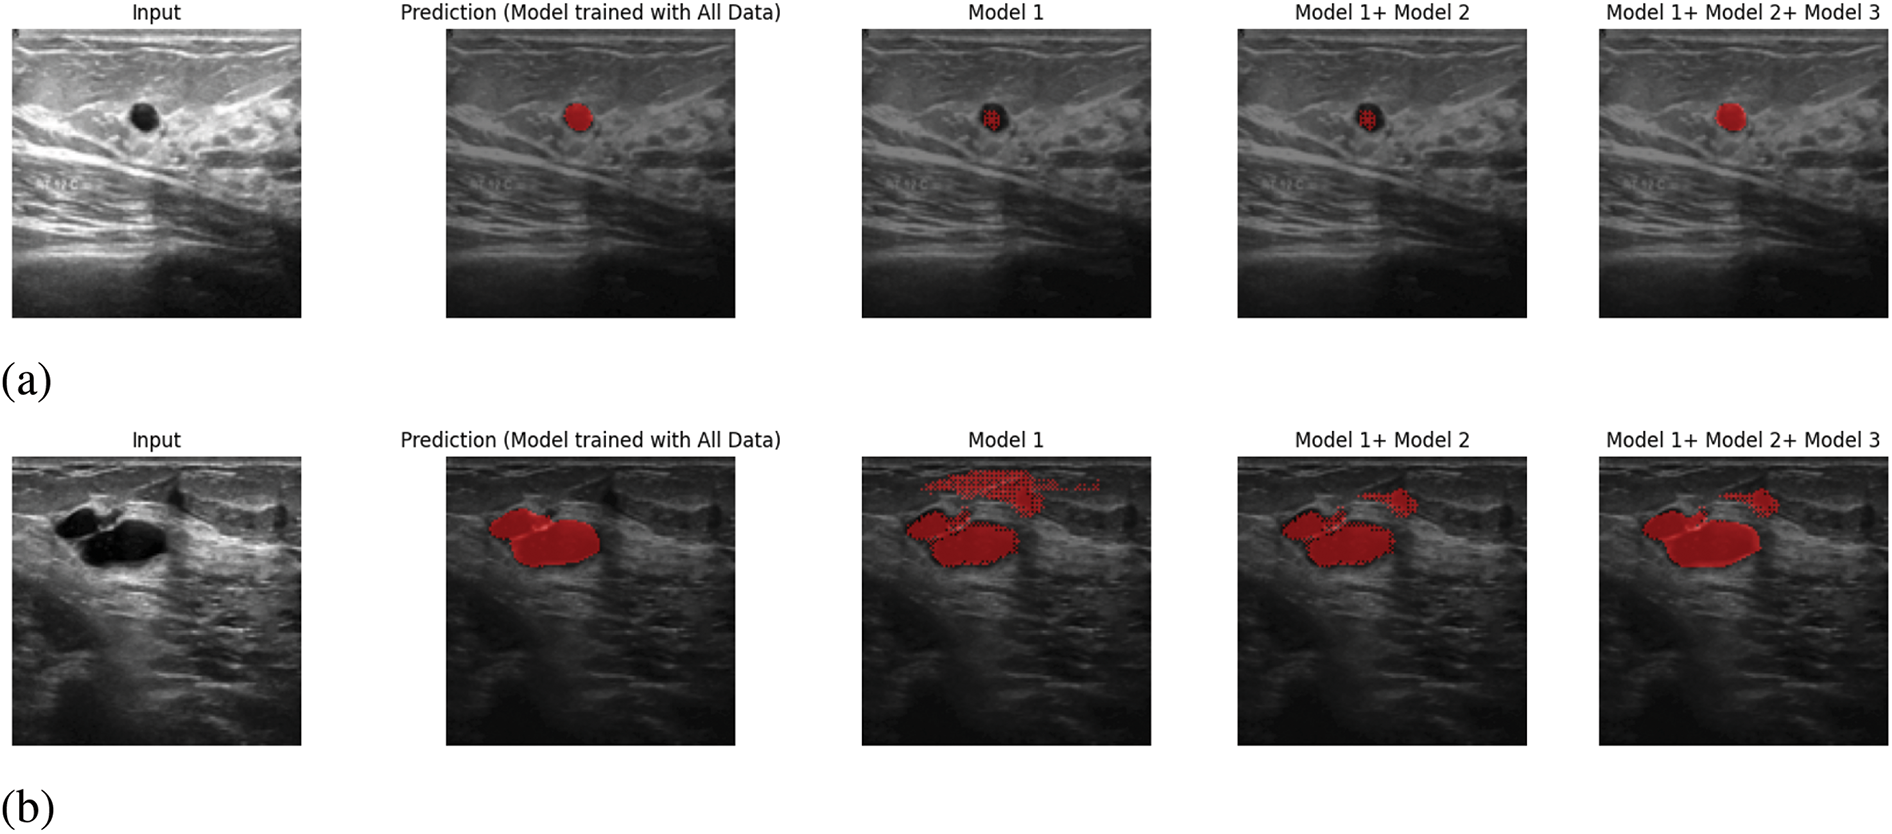

Besides, in Fig. 7, we have provided the voting majority output with Model 1, Model 1 + Model 2, and Model 1 + Model 2 + Model 3. The main objective of presenting this figure is to provide proof of the continuous development of the proposed system. As in the proposed system, it is feasible to add a new trained model to the prediction system that enhances the system’s ability to provide better performance. Whether this proposed system is being able to fulfil this certain objective or not, we have done the voting majority three times, initially with just Model 1. Later, we have done the voting majority with the predictions of Model 1 and Model 2. Finally, this pixel-based voting majority task was done with the predictions of Models 1, 2, and 3. Along with this figure, we have shown a table. In Table 5, we have provided the effectiveness of the ultimate predicted output of Model 1, Model 1+ Model 2, and Model 1+ Model 2+ Model 3 with five inputs based on IoU, Precision, Recall, and F1 score. In this table, it is visible that the voting majority output of model 1 and model 2 is comparatively more accurate than just Model 1. On the other hand, the voting majority output of Models 1, 2, and 3 is better than the combination of Model 1 and Model 2. So, based on the provided information Fig. 7 and Table 5, it can be said that the proposed way of continuous improvement is working successfully according to the plan.

Figure 7: Continuously Developing: (a) Input 1, (b) Input 2, (c) Input 3, (d) Input 4, (e) Input 5